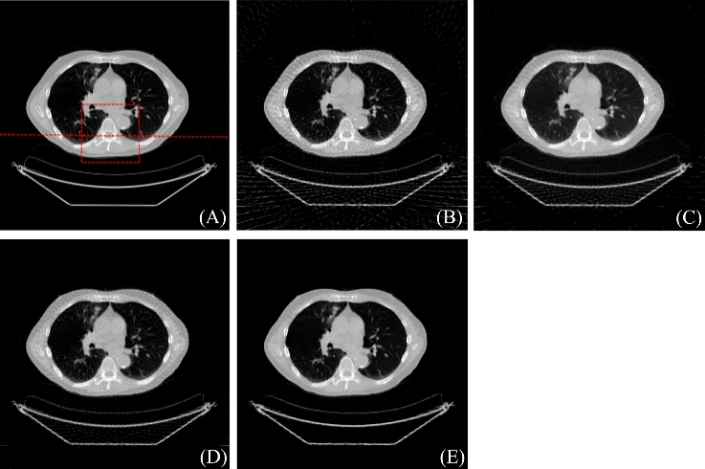

图2:重建结果. (A) 参考图像, (B) FBP重建结果, (C) PWLS-TGV重建结果, (D) R-NLTV重建结果, (E) DD-Net重建结果